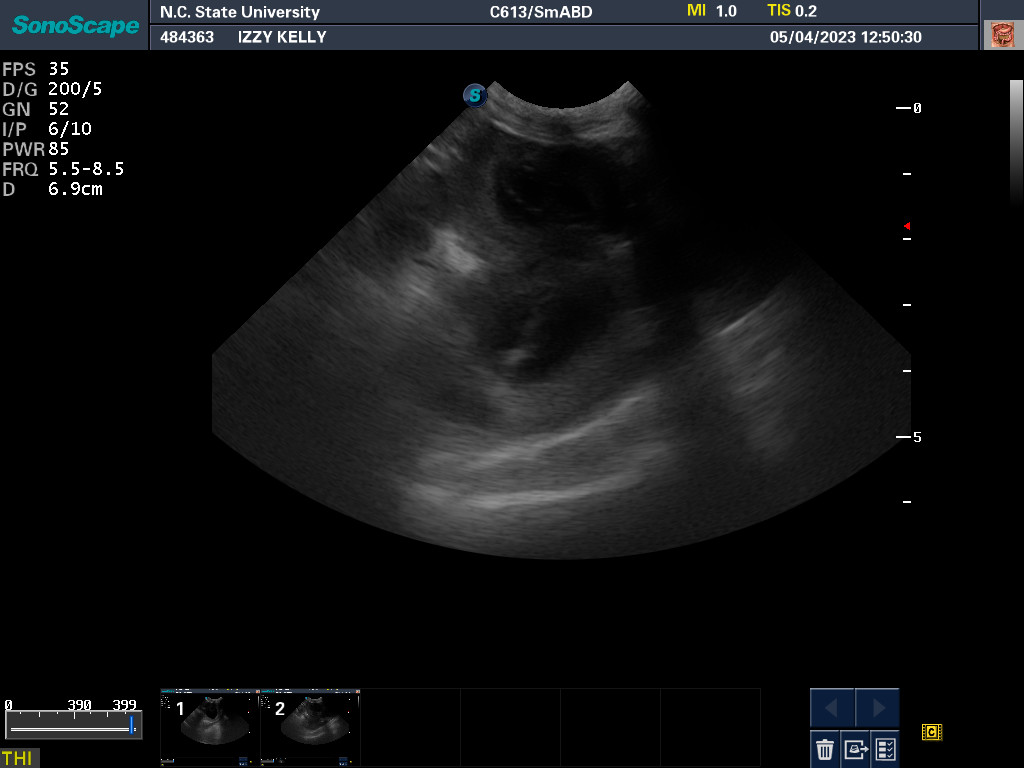

NC State University for an autopsy.